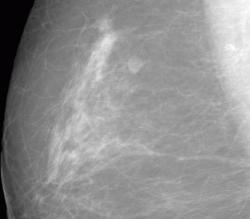

СЛУЧАЙ РЫБАКОВОЙ Л. А. "Инфильтрирующий рак правой молочной железы".

"Инфильтрирующий рак правой молочной железы".

Уважаемая Людмила Александровна, а как вы расцениваете участки, отмеченые желтыми стрелками? нет ли здесь мультицентричного рака?

Каюсь, вина моя. Людмила Александровна указала, что имеется "мультифокальный рост".

Если честно, по поводу жалоб даже не помню, надо амб. карту поднять.Часто бывает,что такие больные ни на что не жалуются, либо незначительная болезненность.В таких случаях не бывает симптома площадки или "лимонной корки",кожа никак не меняется.